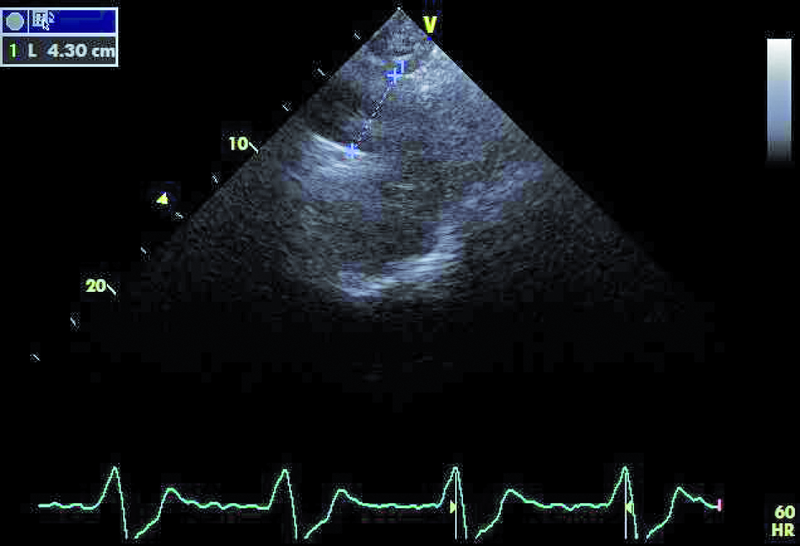

Mężczyzna, lat 35. Jakie patologie można rozpoznać na rycinach?

1. Przerost mięśnia lewej komory (ryc. 1).

2. Przeciek okołozastawkowy – przy przednim brzegu pierścienia zastawki aortalnej (ryc. 1, 2).